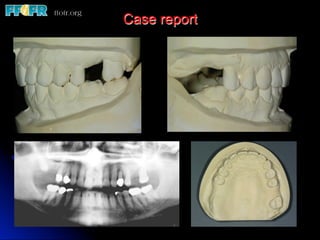

Case report

l  This 49 year old, healthy female presented with multiple tooth loss in

Major issues considered in this patient

l  Provisional restorations

l  Custom abutments

l  Definitive

restorations

l  Occlusion – Anterior group function

l  Patient is 15 years post delivery with

virtually no loss of marginal bone

l  No chipping or fractures of porcelain